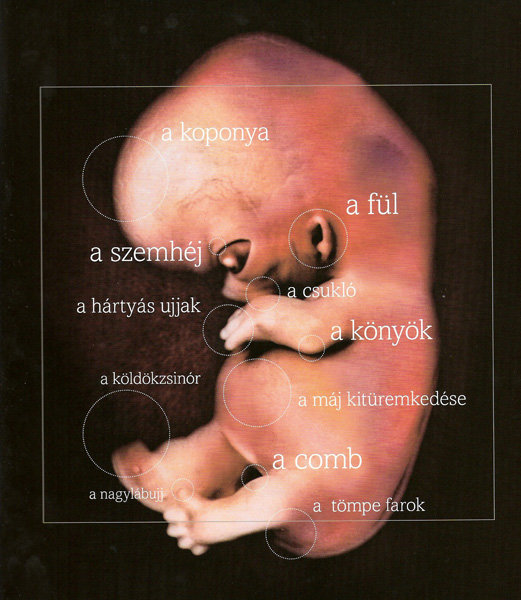

Annus nagyon jók a képek. kis ALien-nek néznek ki... szép az élet...

Annus, nem lehet, hogy a képen, amin 7. hét van. az a 7. terhességi héten készült, és nem a mensitől számítva, mert a táblázat szerint, amit a babanet küldnekem hetente az áll, hogy a 7 hét végén lesz kb 10 mm.

8 mm a baba  11 mm a baba